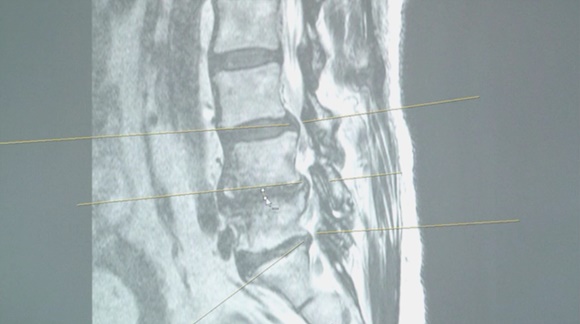

20대의 젊은 환자 김현준 씨가 병원을 찾았다. 허리통증이 느껴지는 것은 물론이고 조금만 걸어도 다리가 당겨서 일상생활이 매우 힘들어진 상태. MRI검사 결과 디스크(추간판 탈출증)가 두 군데나 발생하였다.

이 젊은 환자에게서 허리 디스크(추간판 탈출증)이 발생한 이유는 무엇일까? 명의에서 디스크(추간판 탈출증)이 원인과 더불어 디스크를 불러일으키는 나쁜 자세들에는 어떤 것들이 있는지 알아보도록 하자.